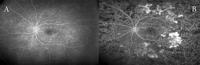

Las causas de pérdida de visión asociadas a la retinopatía diabética pueden deberse tanto a la acumulación de fluido en la mácula (edema macular) como a la isquemia macular secundaria a la oclusión capilar. Ambas circunstancias son fácilmente evaluables por medio de la AFG (

Figura 1).

Figura 1. Retinopatía diabética. A) En el fondo de ojo aparecen lesiones como microaneurismas, exudados duros y algodonosos, que en su conjunto forman el espectro habitual de presentación de la retinopatía diabética. La AFG es clave para el análisis de la extensión y la gravedad tanto de la retinopatía diabética como del edema macular diabético. B) AFG con áreas de isquemia macular. C) SD-OCT: edema macular con desprendimiento del neuroepitelio. D) AFG correspondiente al caso C.